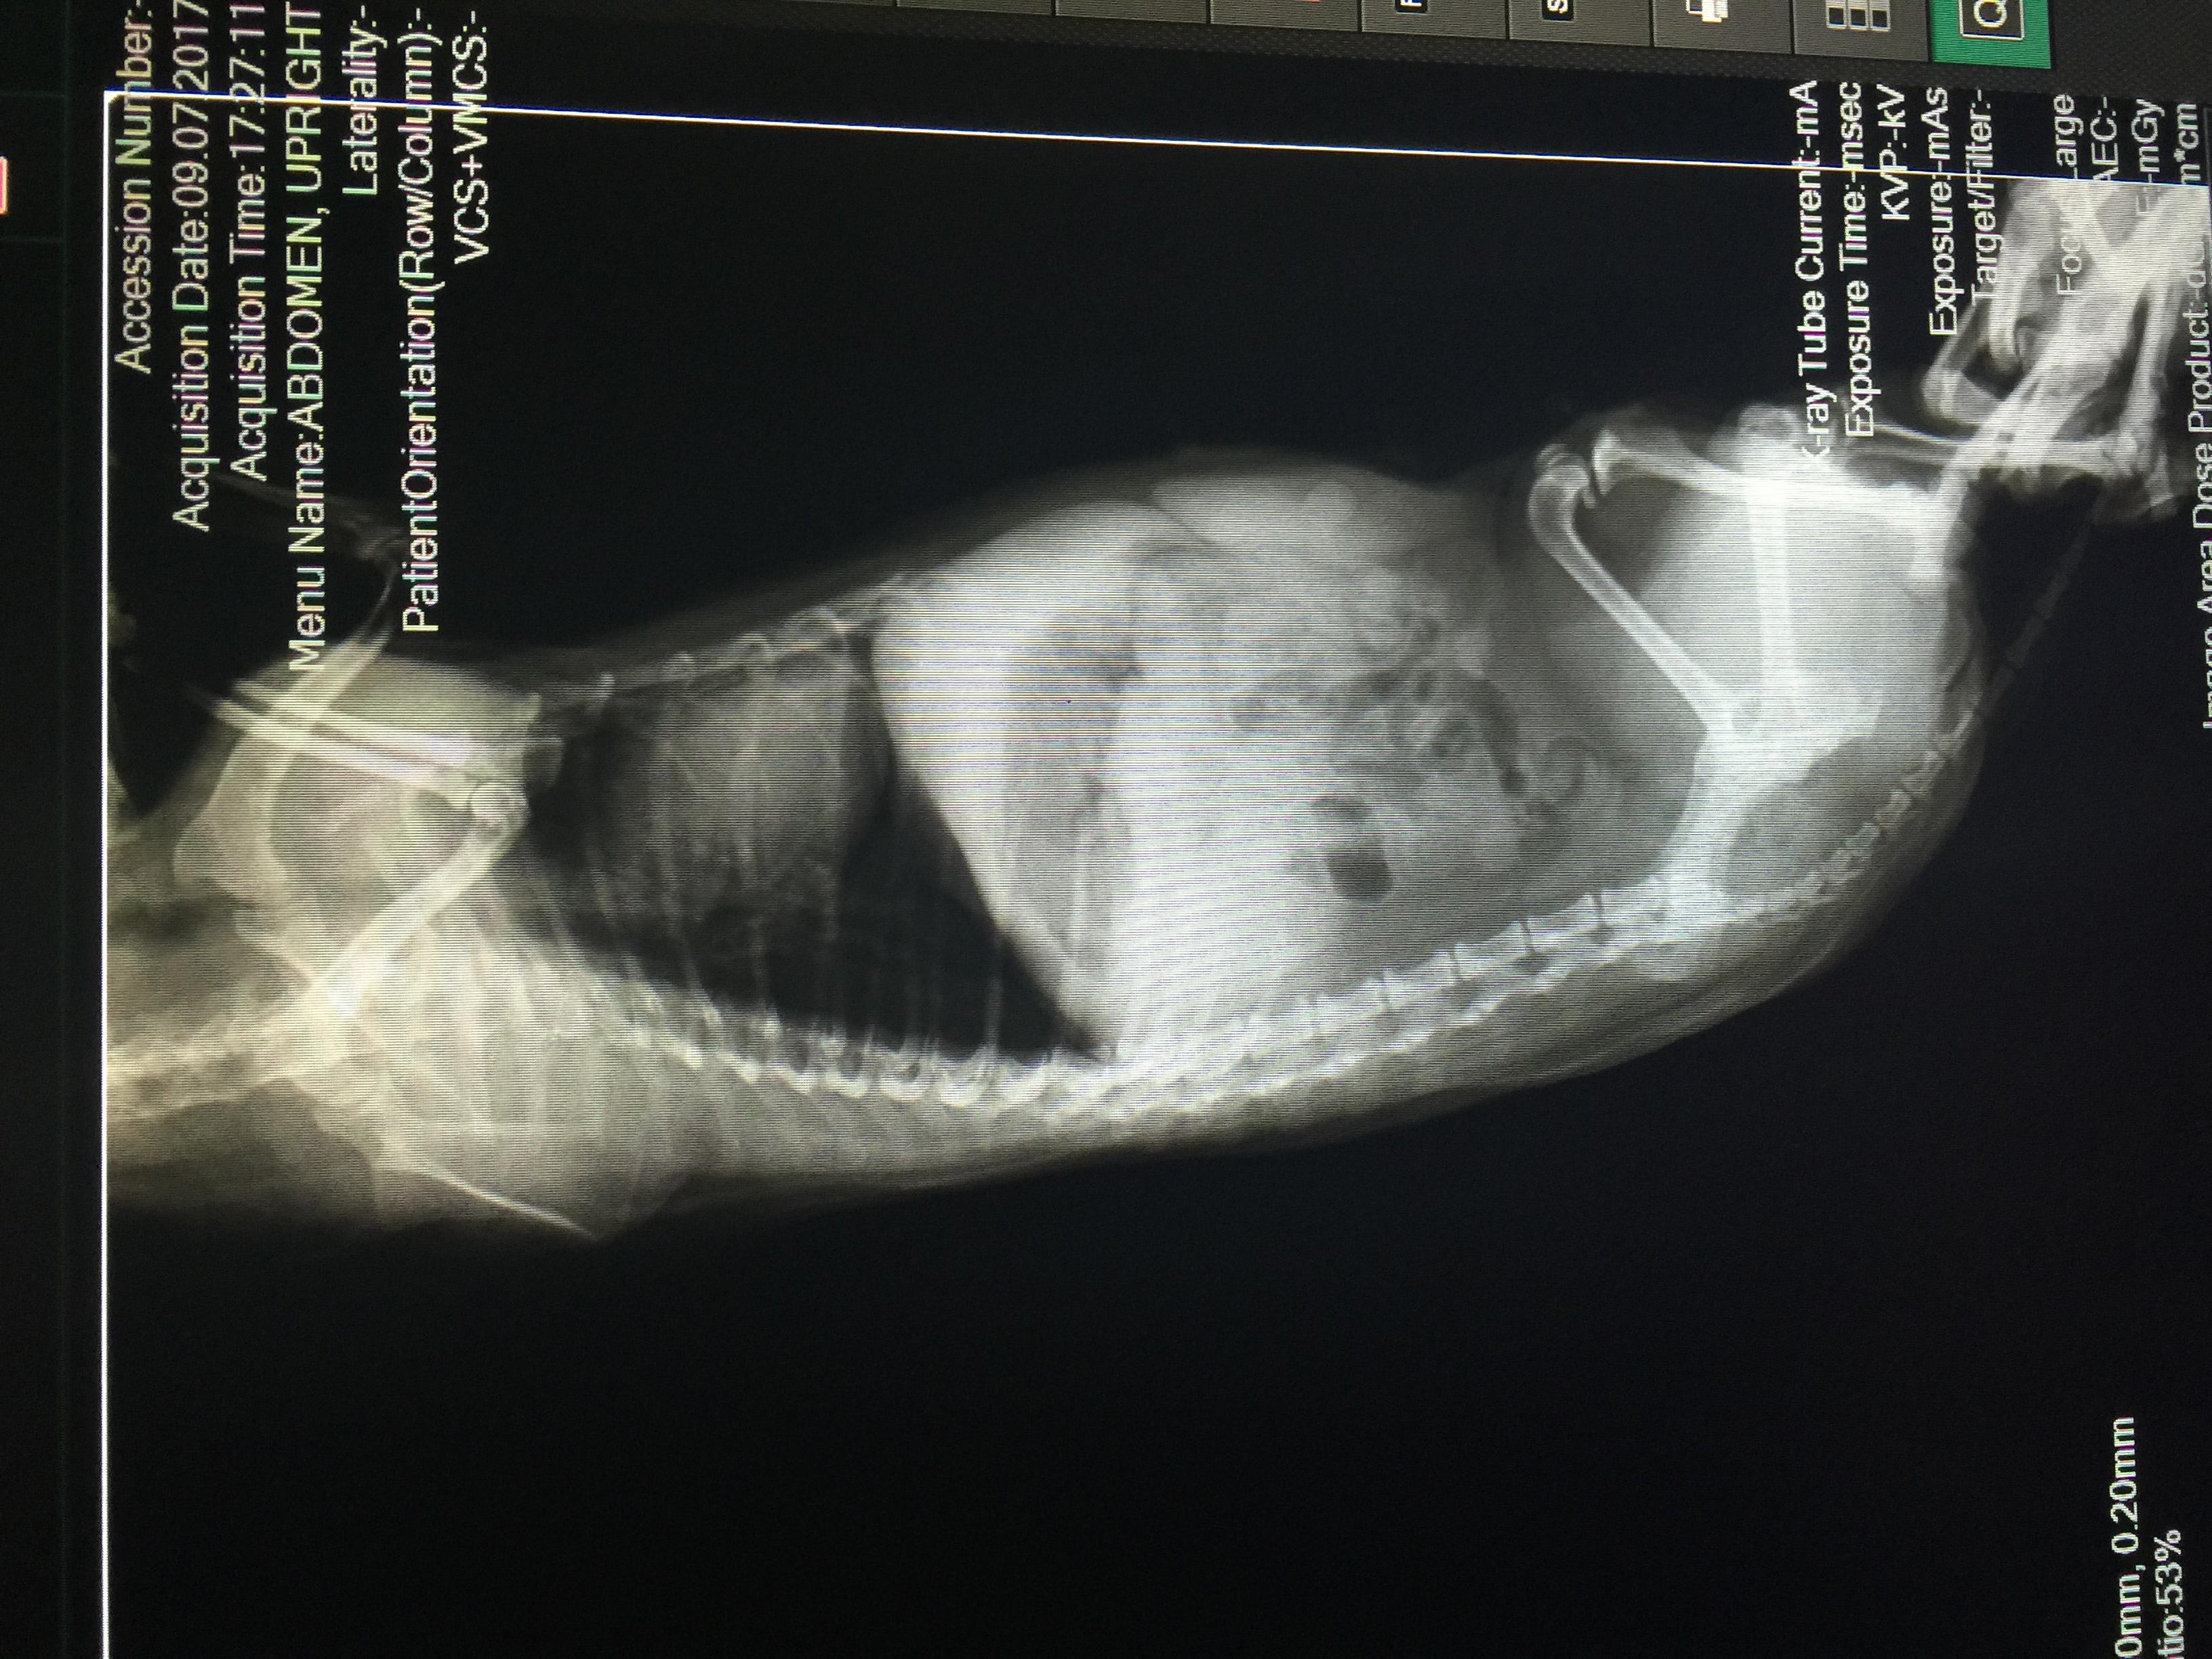

Vet said there's slight inflammation of Maicah's heart, stomach is pushed up -possible pyometra based on her history. See latest xray + old 1/17 sonogram pic attached. Waiting for head vet's feedback based on this am's ultrasound. Maicah is 10-12yo, had 2 CSections- prev. vet did not spay on her last csection, said her uterus was damaged (from prev pregnancies before i adopted her) & there was adhesion so it's risky. How can we get an accurate diagnosis? Is operation still a good option? Thanks!

Unfortunately, the x-rays are not showing up as well here as the originals would, so I'll comment on what I see, but I could easily be missing something. The heart does not appear enlarged, but their are some distended arteries in the x-ray that make me suspicious of heart disease and more specifically heartworm. The abdomen is generally distended and the liver appears somewhat enlarged. This can happen with the heart disease I mentioned or some other condition affecting the liver. I do not see an obvious pyometra on the x-rays or ultrasound (sonogram). I wish I could help you with the other questions, but it's impossible without me knowing the cat's full history, or having the opportunity to examine the cat myself. One thing we can offer on Petco Pet Education Center, formerly Petcoach is a consultation. This is a service that you would have to pay for, but it would allow you to text back-and-forth with one of our experts and send as many pictures as you want. With these consultations, we can help to identify the problems by gaining all the necessary information. Otherwise, you may seek a second opinion from another veterinarian in your area. I hope this is somewhat helpful and everything turns out OK Maicah.